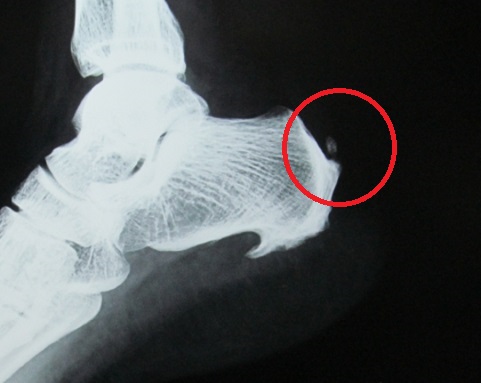

アキレス腱断裂は日常生活でも起こる! 症状や痛み、検査方法についてご紹介!

アキレス腱から延びて、ふくらはぎの筋肉につながる部分を断裂してしまいました。